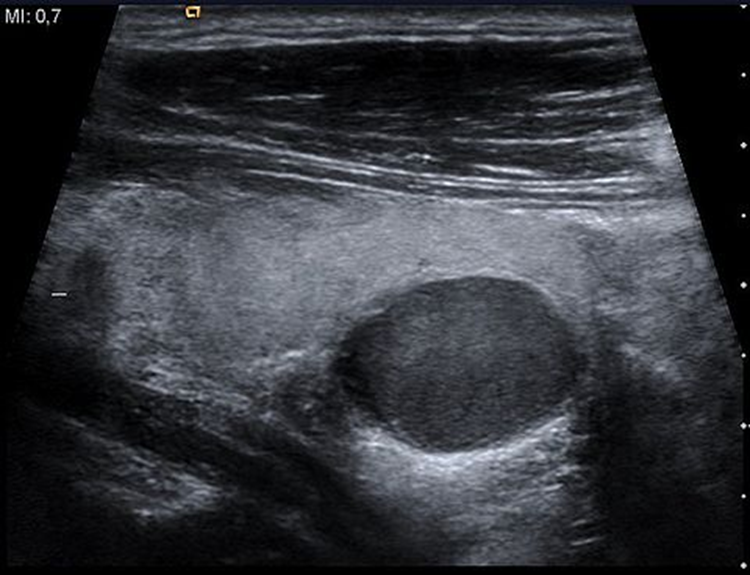

Adenoma:

is a benign lesion . It is well defined and hypo echoic.

Parathyroid adenoma.